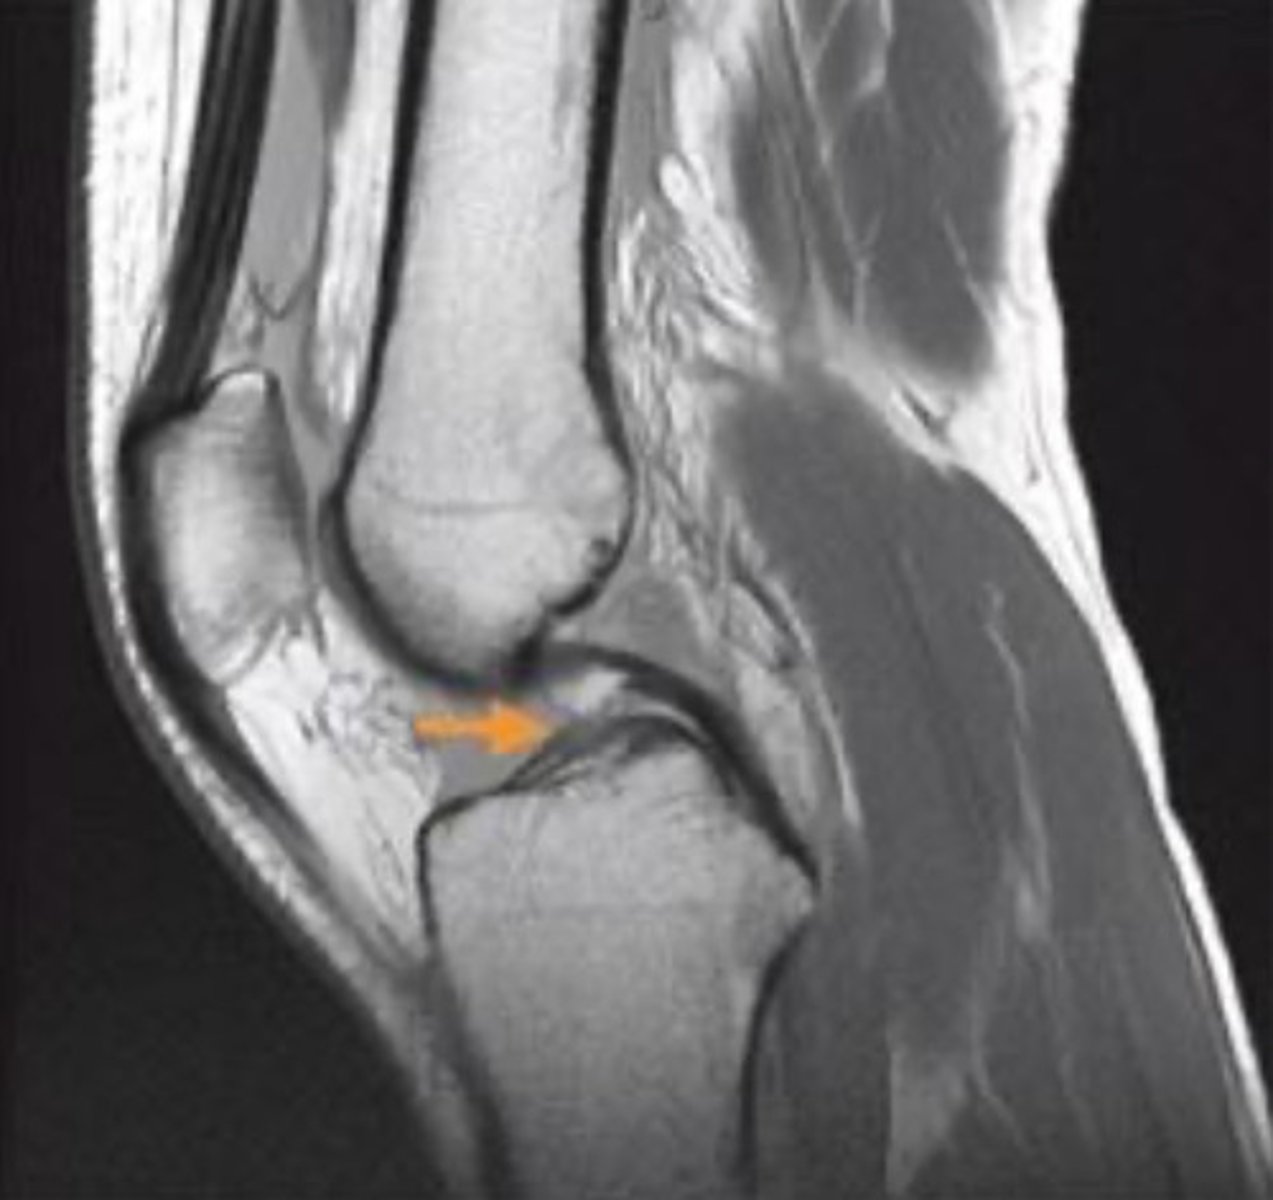

what structure is indicated by the orange arrow?

anterior cruciate ligament

identify the view of this magnetic resonance image (MRI)

sagittal view

what grade would you classify the ligamentous tear in this MRI?

full-thickness